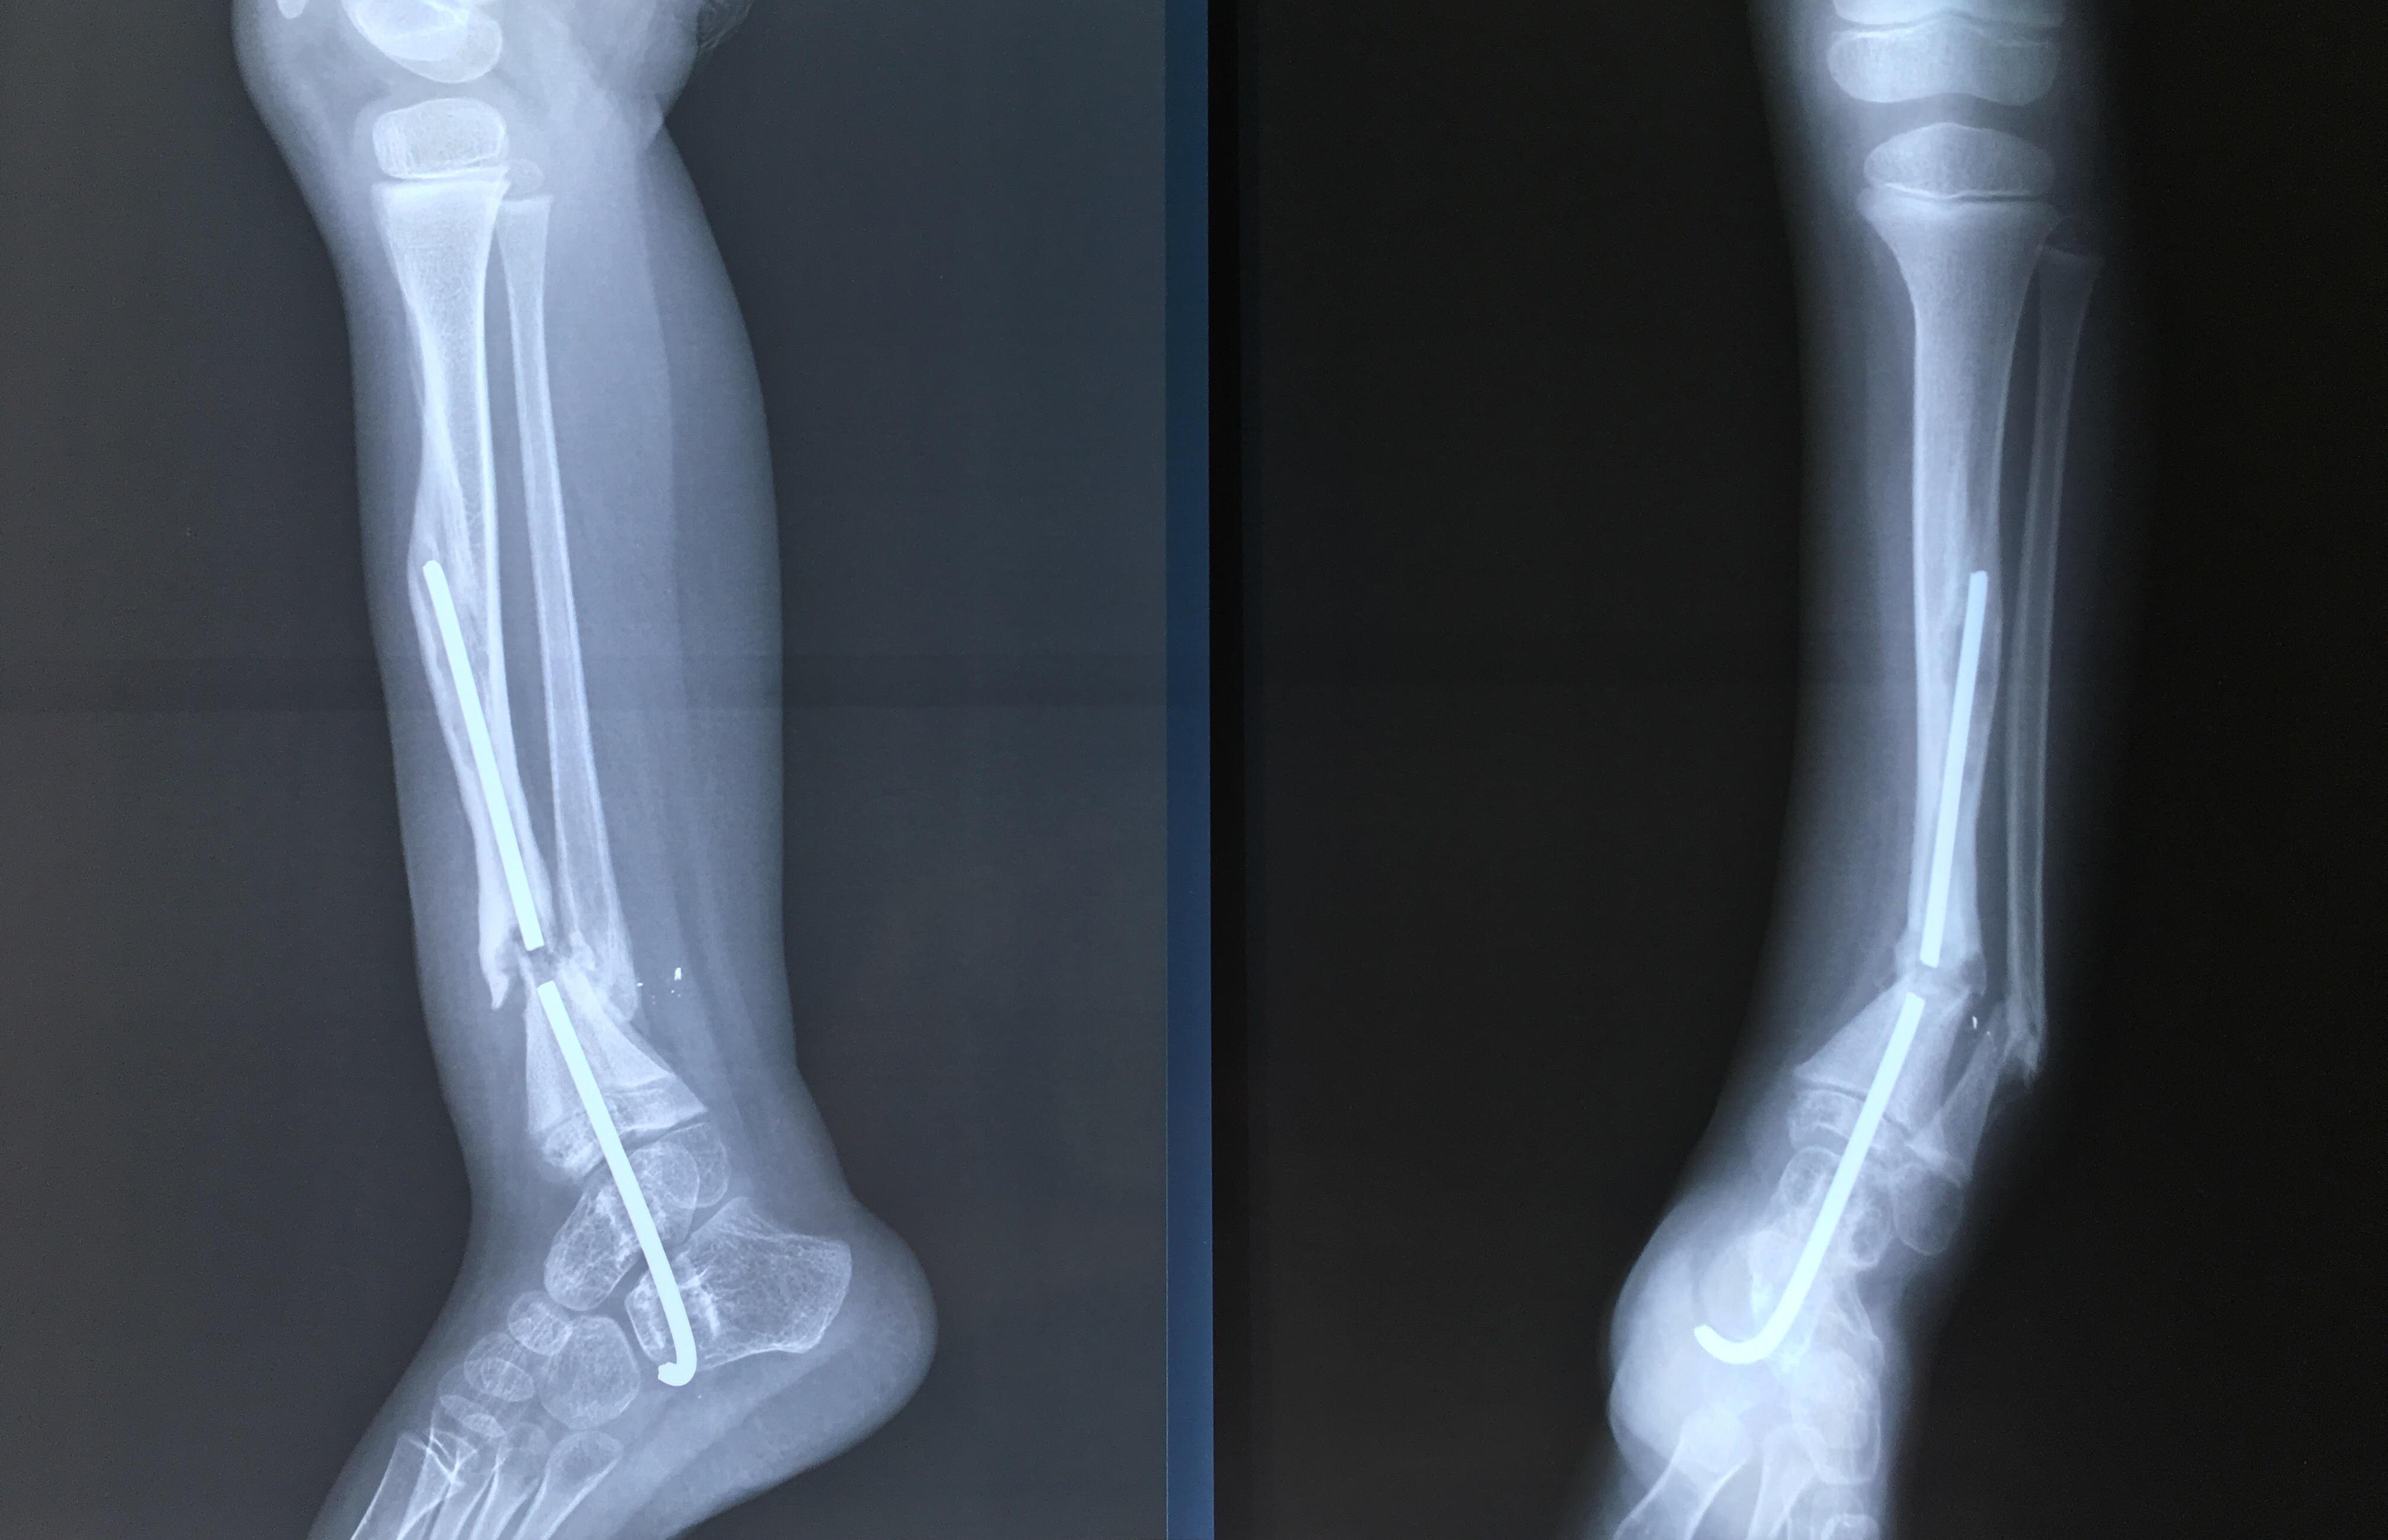

Phẫu thuật thành công ca bệnh hiếm gặp...khớp giả bẩm sinh xương chày

26/06/2019 17:00

Đã xem: 3366

Bệnh viện Chấn thương- Chỉnh hình Nghệ An, vừa phẫu thuật thành công cho bệnh nhi khớp giả bẩm sinh xương chày